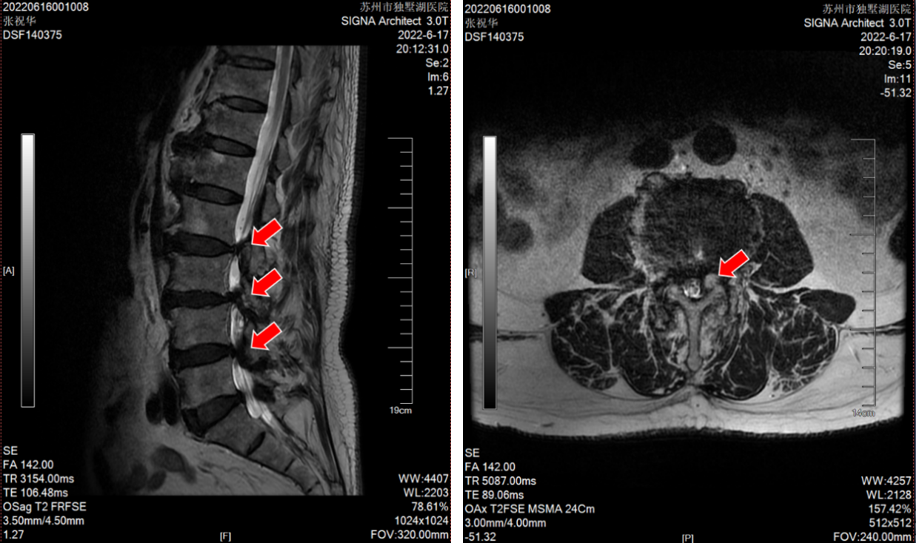

张老爷子今年84岁高龄了,家住盐城建湖。之前老人家身子骨一直硬朗,吃得好,睡得香,直到近年腰腿痛再次发作,如今已经发展到了几乎寸步难行的程度。说起来,这位老爷子算是姜主任的“老熟人”了,二十多年前他就曾因“腰椎间盘突出症”在苏州接受过姜主任的手术,术后恢复良好。但近几年,随着年龄增长,老爷子的腰椎疾患又犯了,且加重很快。这次在他两个儿子的陪同下,特地从外地赶来独墅湖医院,希望姜主任能给他解决病痛。姜主任仔细检查后发现:老先生腰椎退变严重,患的是一种名叫“腰椎管狭窄症”的疾病。表现为“腰腿痛”和“间歇性跛行”的症状,需要做彻底的“椎管扩大减压+椎弓根螺钉内固定+椎间融合术”。刚讨论完老先生的病情,患者的小儿子说:“给我哥看看吧,他也挂了您的号,是颈椎病,可能也要手术。”姜主任分析过病情后确认患者得了一种称为“后纵韧带骨化症”的颈椎病,几年前就已确诊,因为害怕手术不成功会导致瘫痪,一直拖到现在,已经严重到难以独立行走。这次下定决心与老父亲一起来苏州接受手术。由于床位紧张,老先生首先住进医院接受了手术。手术很顺利,术后仅仅两天,他已经可以下床活动,双下肢症状明显缓解。

(腰椎MRI提示L2-5椎间盘突出,椎管狭窄明显)

(颈椎CT显示张先生C2-6椎体后纵韧带广泛骨化,椎管狭窄明显)

(颈椎MRI提示C2-6椎管狭窄,脊髓受压严重)